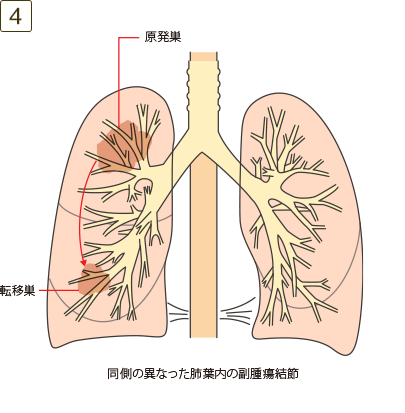

充実成分径>5cmでかつ≦7cm、または充実成分径≦5cmでも以下のいずれかであるもの・壁側胸膜、胸壁(superior sulcus tumor を含む)、横隔神経、心膜のいずれかに直接浸潤・同一葉内の不連続な副腫瘍結節

充実成分径>7cm、または大きさを問わず横隔膜、縦隔、心臓、大血管、気管、反回神経、食道、椎体、気管分岐部への浸潤、あるいは同側の異なった肺葉内の副腫瘍結節